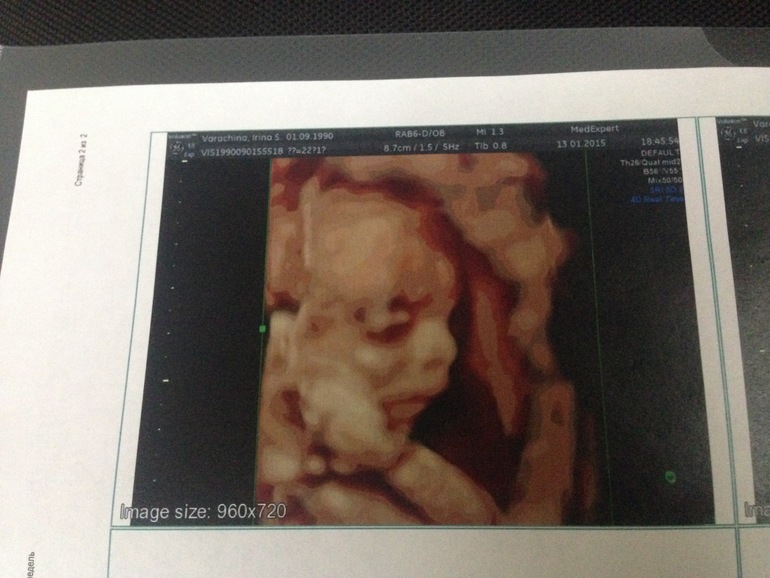

Самое главное, что с ним всё хорошо!!! Мы развиваемся на 21 недельку, измерили нас, все параметры в норме, взвесили, мы весим 449 грамм! Воды в норме, обвития нет, шейка моя удлиннилась с 2,3 до 3,4 см, плацента поднимается, была 2,5 стала 4 см! Находится в тазовом предлежании, пинает маму в мочевой пузырь)))) Пипирку нам показал, ручкой помахал, но всё же был суров и недоволен вторжением, сделал очень серьезное выражение лица, от чего мы очень смеялись

вот такой у нас малышок) ну и наше фото серьезного мужчины, который подложив под голову руку как бы намекает: ну и что вам от меня опять надо?